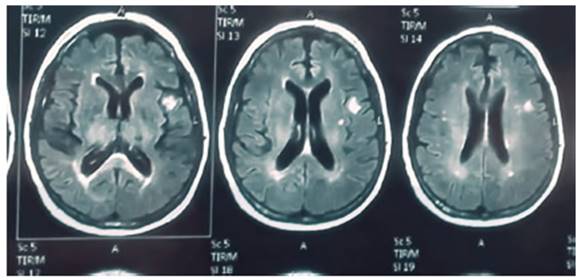

– sulfametoxasol (TMS). Resonancia magnética

nuclear (RMN) de encéfalo: En la zona temporal subcortical izquierda se

observa una imagen nodular hiperintensa con realce en

anillo de 10 mm de diámetro, que presenta restricción de la

difusión vinculable con absceso (Figura 2).